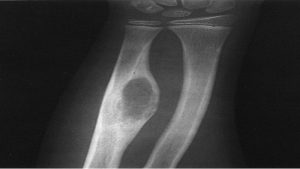

Người bệnh bị u xương có nguy hiểm không?

U xương là một bệnh lý liên quan đến sự phát triển bất thường của...